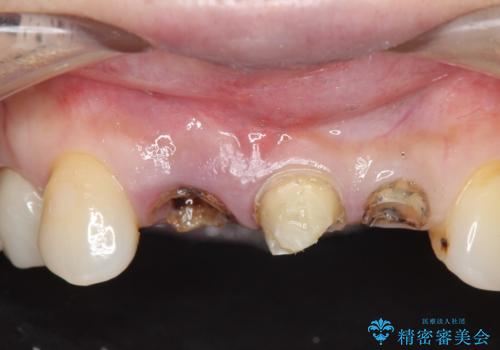

- 下顎前歯部の突き上げで上顎前歯の被せ物が土台ごと外れてしまった方の症例です。

右上1番目の歯は根元まで割れてしまっており、保存不可能だったため抜歯となりました。

抜歯後、骨と歯肉の回復を待ち、オールセラミッククラウンによるブリッジで補綴を行いました。